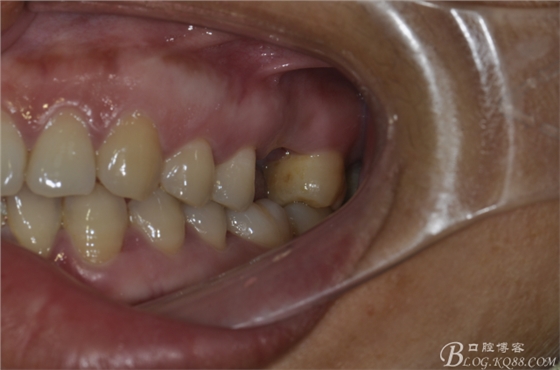

患者唐某某,男,50歲,要求種植修復(fù)左上缺失大牙。

術(shù)前口內(nèi)照片。上頜竇外提一例